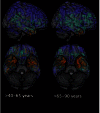

White matter hyperintensities are associated with increased risk of dementia and cognitive decline. The current study investigates the relationship between white matter hyperintensities burden and patterns of brain atrophy associated with brain ageing and Alzheimer's disease in a large populatison-based sample (n = 2367) encompassing a wide age range (20-90 years), from the Study of Health in Pomerania. We quantified white matter hyperintensities using automated segmentation and summarized atrophy patterns using machine learning methods resulting in two indices: the SPARE-BA index (capturing age-related brain atrophy), and the SPARE-AD index (previously developed to capture patterns of atrophy found in patients with Alzheimer's disease). A characteristic pattern of age-related accumulation of white matter hyperintensities in both periventricular and deep white matter areas was found. Individuals with high white matter hyperintensities burden showed significantly (P < 0.0001) lower SPARE-BA and higher SPARE-AD values compared to those with low white matter hyperintensities burden, indicating that the former had more patterns of atrophy in brain regions typically affected by ageing and Alzheimer's disease dementia. To investigate a possibly causal role of white matter hyperintensities, structural equation modelling was used to quantify the effect of Framingham cardiovascular disease risk score and white matter hyperintensities burden on SPARE-BA, revealing a statistically significant (P < 0.0001) causal relationship between them. Structural equation modelling showed that the age effect on SPARE-BA was mediated by white matter hyperintensities and cardiovascular risk score each explaining 10.4% and 21.6% of the variance, respectively. The direct age effect explained 70.2% of the SPARE-BA variance. Only white matter hyperintensities significantly mediated the age effect on SPARE-AD explaining 32.8% of the variance. The direct age effect explained 66.0% of the SPARE-AD variance. Multivariable regression showed significant relationship between white matter hyperintensities volume and hypertension (P = 0.001), diabetes mellitus (P = 0.023), smoking (P = 0.002) and education level (P = 0.003). The only significant association with cognitive tests was with the immediate recall of the California verbal and learning memory test. No significant association was present with the APOE genotype. These results support the hypothesis that white matter hyperintensities contribute to patterns of brain atrophy found in beyond-normal brain ageing in the general population. White matter hyperintensities also contribute to brain atrophy patterns in regions related to Alzheimer's disease dementia, in agreement with their known additive role to the likelihood of dementia. Preventive strategies reducing the odds to develop cardiovascular disease and white matter hyperintensities could decrease the incidence or delay the onset of dementia.